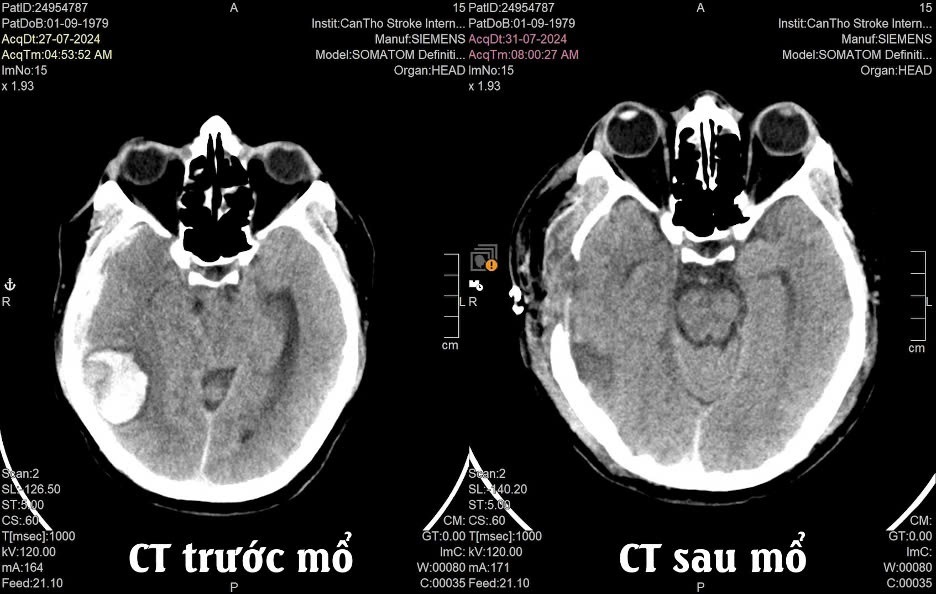

Các xét nghiệm chẩn đoán hình ảnh cho thấy bệnh nhân bị xuất huyết não nặng, với chảy máu dưới lớp màng não ở phía bên phải và một khối dị dạng bất thường trong não. Ê-kip các bác sĩ đã quyết định thực hiện phẫu thuật cấp cho bệnh nhân.

“Trường hợp của bệnh nhân này, chúng tôi đã tiến hành phẫu thuật mở sọ để lấy khối máu tụ, cầm máu và loại bỏ khối mạch máu bất thường. Khối dị dạng mạch máu khoảng 2cm đã được loại bỏ trong phẫu thuật. Mô xương sọ được lưu trữ tại ngân hàng mô, và dự kiến có thể ghép lại trong vòng 3 tháng khi bệnh nhân hoàn toàn ổn định”, bác sĩ Thái cho hay.

Chỉ sau 3 ngày phẫu thuật, bệnh nhân đã tỉnh và phản ứng rất tốt với điều trị. Sau 10 ngày, bệnh nhân được xuất viện với sức khỏe ổn định, phục hồi hoàn toàn trong niềm vui của bản thân, gia đình và đội ngũ bác sĩ.